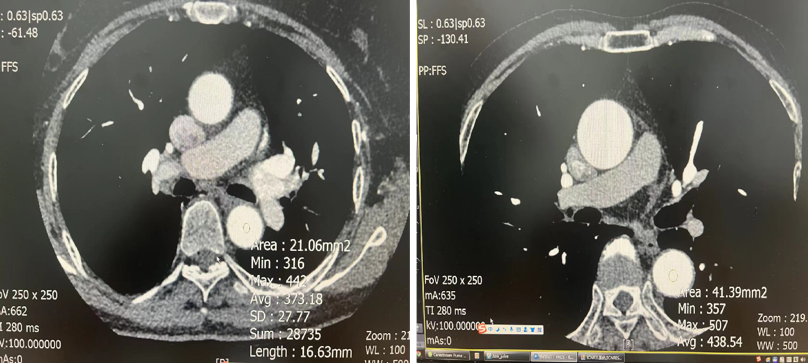

血管CTA:相同体重的患者 造影剂用320mg/ml和370mg/ml 都用4.0ml/s流速注射60ml对比剂

从上述图像可以看出,370造影剂明显比320造影剂CT值要高,显示要好